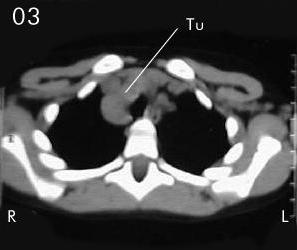

Tomografía torácica

Estudio Tomográfico tórax completo: En detalles los cortes progresivos desde el manubrio esternal hasta 2 cm sub carinal traqueal. (vistas desde el abdomen), (R) = derecho , (L) = Izquierdo; no se apreciaron procesos en pleura ni parenquima pulmonar.

En Mediastino antero superior:

Corte 04: observe la extensión a ambos lados de la traquea a su nivel supra carinal y su compresión en el eje transverso de sus paredes.

Corte 05 y Corte 06: extensión peritraqueal y subcarinal de la lesión, bien limitada sin infiltración de estructuras vecinas.